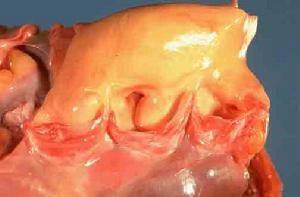

3.缺血性損傷輕輕度Ⅱ型SMI病人,其發作可能是因為其心肌缺血嚴重程度較輕,缺血範圍較小,持續時間較短。有些SMI病人在24h連續ECG描記中,較短時間的心肌缺血呈現為無症狀;而較長時間的心肌缺血有心絞痛,但也有人發現ST段變化在有痛和無痛者無顯著差別。因此,尚不清楚是以上3種可能性中那一點,還是3種可能性聯合在SMI的發作中起主要作用,也可能是多因素參與的結果,但其確切機制尚待闡明。無症狀型冠心病患者,病理學檢查心肌無明顯組織形態學改變,此時冠狀動脈出現內皮細胞輕度受損,血小板黏附、結締組織增生,平滑肌細胞輕度增殖或移位,脂質沉積,冠狀動脈管腔呈現輕度狹窄,心肌缺血。